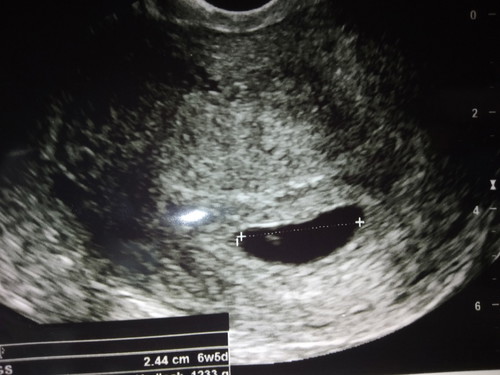

6w5d

พึ่งเจอน้องค่ะ 6w5d คุณหมอบอกระวังแท้ง น้องเล็กไปรึป่าว กังวลมาก ค่ะ ขอดูแม่ซาวด์น้องตอน 6w หน่อยได้ไหมค่ะ ว่าน้องตัวเท่าไหน?